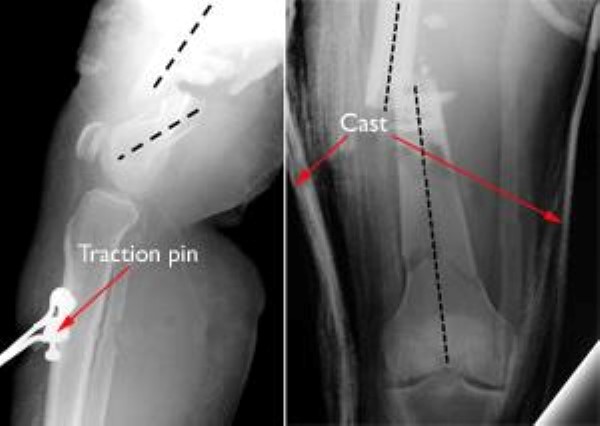

• Skeletal traction. Skeletal traction is a pulley system of weights and counterweights that holds the broken pieces of bone together. A pin is placed in a bone to position the leg.

• Casting and bracing. Casts and braces hold the bones in place while they heal. In many cases of distal femur fracture, however, a cast or brace cannot correctly line up the bone pieces because shortened muscles pull the pieces out of place. Only fractures that are limited to two parts and are stable and well aligned can be treated with a brace.

Because traction, casting, and bracing do not allow for early knee movement, they are used less often than surgical treatments. Your doctor will talk with you about the best treatment option for you and your injury.

Distal femur fractures treated with traction and casting

These fractures treated with traction (left) and casting (right) are not lined up and will not successfully heal.